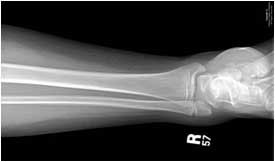

- Low need – an x-ray of a broken ankle